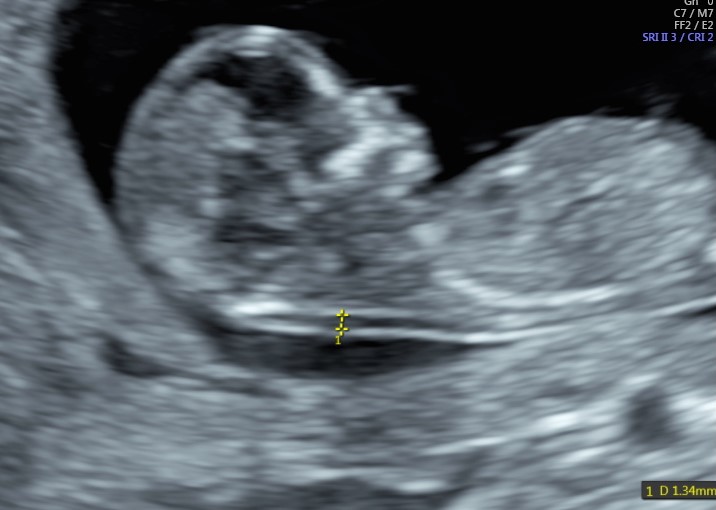

Indipendentemente dalla nostra scelta, è di capitale importanza fare comunque una ecografia fra la 11° e la 13° settimana. Infatti già a questa epoca gestazionale siamo in grado di condurre un’iniziale valutazione morfologica. Ma soprattutto questo è la finestra di opportunità per studiare la translucenza nucale. In realtà questa ampia finestra di tre settimane ha il suo momento più favorevole a 11 settimane e mezza e inizio dodicesima.

Si va a misurare quindi attraverso una ecografia lo spazio dietro la nuca: è una fisiologica raccolta di linfa che tende ad aumentare in diverse situazioni patologiche risultando essere un indice generale di buon andamento della gravidanza dove più è sottile più siamo tranquilli a riguardo di patologie cromosomiche, malformazioni cardiache, ed alcune malattie genetiche.